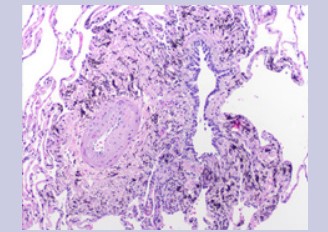

Physical exam was benign. Complete blood count and immunological panel were within normal limits. Spirometry, lung volumes and diffusion capacity were within normal limits. Chest x-ray (Figure 1) showed faint reticular opacities prominent in the mid to lower lobes. Computed Tomography (Figure 2) of the chest showed a diffuse mosaic attenuation pattern. There were multiple pulmonary nodules noted in the right middle lobe. There was no lymphadenopathy. Transthoracic echocardiogram showed impaired left ventricular relaxation with normal LV ejection fraction. Bronchoscopy and transbronchial biopsies of the right upper, middle and lower lobes were performed. Histopathology (Figure 3, Figure 4) revealed mild, nonspecific chronic inflammation. Acid-fast bacilli and fungal stains were negative. There was no evidence of malignancy. Given the persistent symptoms and abnormal CT findings, wedge biopsy of the right upper, middle and lower lobes was performed. Wedge resections showed alveolated lung with expansion of peribronchiolar interstitium by black dust-laden macrophages and dust macules. There were areas of peribronchiolar fibrosis with birefringent silicate and silica material within the interstitium and macrophages. Based on her history of exposure to stone grinding, charcoal and wood burning stoves along with the histopathologic findings consistent with mixed dust pneumoconiosis, she was diagnosed with "Hut Lung” or Domestically Acquired Particulate Lung Disease.

Figure 4: Histopathology showing non-specific granulomatous inflammation.